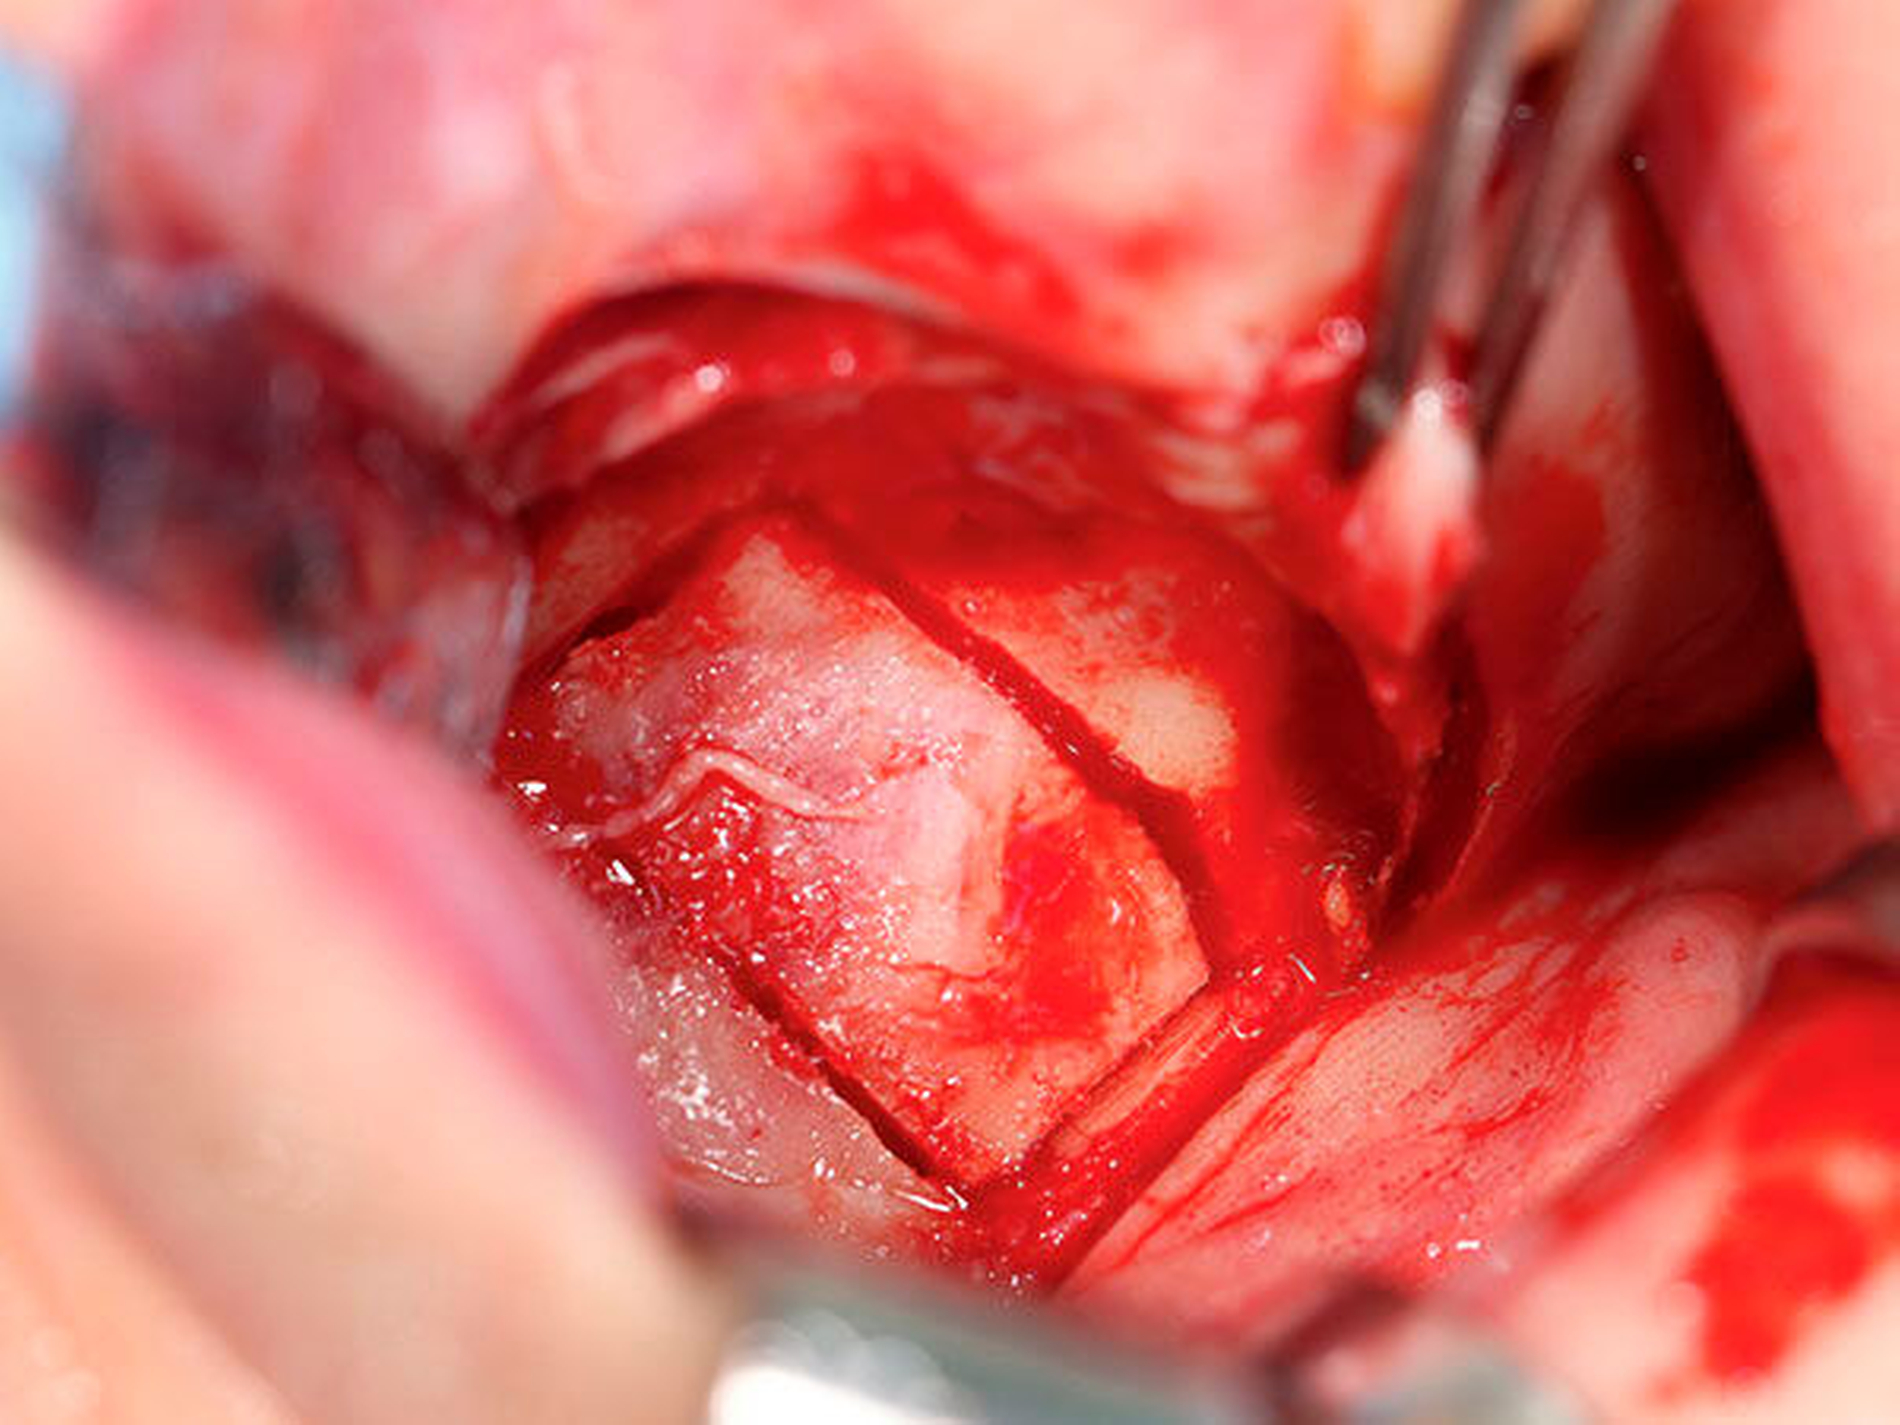

Bei Vorliegen einer Raumforderung der rechten Kieferhöhle unklarer Genese stellte der behandelnde Chirurg die Indikation zur Exzision des Befunds in Intubationsnarkose. Zur Darstellung der vorderen Kieferhöhlenwand wurde im Bereich 12 bis 15 paramarginal inzidiert und der Sinus maxillaris mittels eines gefensterten Zugangs eröffnet. Es stellte sich eine, die gesamte rechte Kieferhöhle ausfüllende, knöcherne Struktur dar (Abbildung 4). Nachdem der Befund aufgrund seiner Größe separiert worden war, wurde er geborgen (Abbildung 5) und zur pathologischen Untersuchung eingesandt (Abbildung 6). Teile der medialen Kieferhöhlenwand und des Orbitabodens waren durch die vorliegende Strukturveränderung resorbiert. Nach Spülung der Wunde und endoskopischer Sicherung einer offenen Verbindung zum mittleren Nasengang wurde dort zur Retention der Abflusswege eine Tamponade eingelegt und über das rechte Nasenloch ausgeleitet.